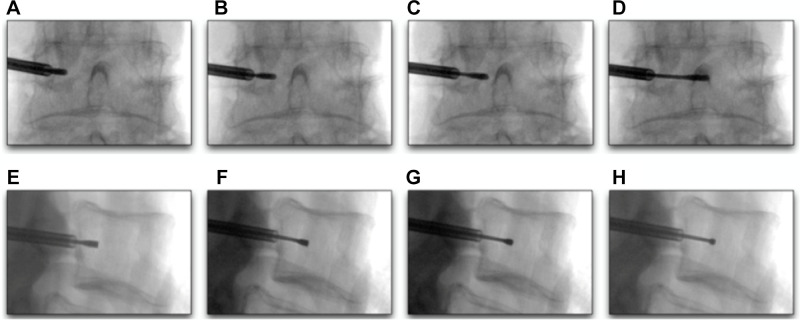

3. Transpedicular approach: A curved introducer is advanced through the pedicle into the vertebral body under fluoroscopic guidance

4. RF probe deployment: The probe is deployed to the midline of the vertebral body where the BVN is located

Transpedicular Approach:

• The introducer needle (typically 8G) enters at the superior-lateral aspect of the pedicle and advances toward the inferior-medial aspect

• Frequent alternating between true AP and true lateral imaging is essential to avoid breaching the pedicle cortex

• Goal: reach the posterior vertebral body in the lateral view before reaching the medial or inferior pedicle walls in the AP view

Channeling Through Bone:

• A critical distinction from soft-tissue procedures: bone channeling is not forgiving — each advancement creates a permanent channel

• The curved nitinol channeling stylet is advanced in approximately 2 mm increments with measured mallet taps

• Direction is adjusted by rotating the cannula hub and curved channeling assembly as a single unit

• If the curved stylet progresses too posteriorly (within 1 cm of the posterior wall), switch to the straight channeling stylet